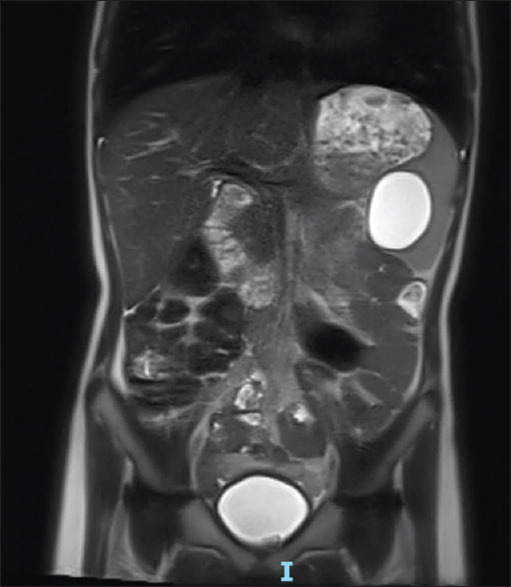

摘要:脾表皮样囊肿是一种罕见的儿童良性肿瘤,占脾脏所有囊性病变的 10%,是非寄生虫性脾囊肿中最常见的诊断方法。它可能是偶然发现的,也可能是在肿块或腹痛的影像检查后发现的。由于全脾切除术使患者面临脾切除术后感染的风险,腹腔镜脾部分切除术在过去二十年中越来越受欢迎,因为它保留了脾脏的免疫功能。由于出血风险较高,这项技术只能由训练有素的团队进行。作者报告了三例接受腹腔镜脾脏部分切除术的患者:一名无相关病史的 7 岁女孩,脾脏下极有一个 4.5 厘米大的表皮样囊肿;一名接受胰岛素治疗的 13 岁 1 型糖尿病男孩,脾脏上极有一个 7 厘米大的表皮样囊肿;一名无病史的 14 岁女孩,脾脏上极有一个 6 厘米大的表皮样囊肿。手术时间分别为2小时30分钟、3小时和4小时30分钟。术中失血量分别为 100 毫升、350 毫升和 300 毫升。每位患者的住院时间均为 6 天。围手术期未进行输血。平均随访时间为 21 个月(分别为 32 个月、21 个月和 10 个月),没有发生并发症或复发。

Abstract: Epidermoid splenic cyst is a rare benign tumour in children, accounting for 10% of all cystic lesions of the spleen and is the most common diagnosis of non-parasitic splenic cysts. Its discovery could be incidental or happen after an imaging workup for a mass or abdominal pain. Since total splenectomy exposes a patient to the occurrence of overwhelming post-splenectomy infection, laparoscopic partial splenectomy has been increasingly popular over the past two decades because it preserves the immune function of the spleen. This technique should only be performed by a well-trained team because of the high risk of bleeding. The authors report the cases of three patients who underwent laparoscopic partial splenectomy: a 7-year-old girl with no relevant history with a 4.5-cm epidermoid cyst involving the lower pole of the spleen, a 13-year-old boy, type 1 diabetic on insulin therapy, with a 7-cm epidermoid cyst of the upper pole of the spleen and a 14-year-old girl, with no previous history, with a 6-cm upper pole epidermoid splenic cyst. Operating times were 2 h 30 min, 3 h and 4 h 30 min, respectively. The intraoperative blood loss was 100 mL, 350 mL and 300 mL, respectively. The length of hospital stay was 6 days for each patient. No blood transfusion was performed perioperatively. With a mean follow-up duration of 21 months (32 months, 21 months and 10 months, respectively), no complication or recurrence occurred.